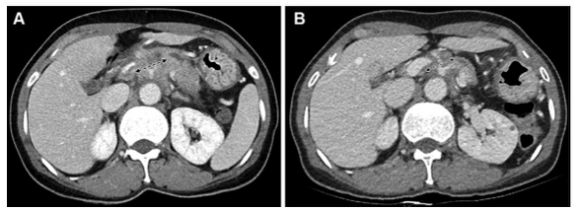

一名54歲胰腺導管腺癌患者的圖像,為第一組的代表性病例(CT和CA 19-9反應者)。(A) 基線對比增強CT圖像顯示胰腺體部有一個30毫米的腫塊,腹腔動脈和肝總動脈被包圍(箭頭)。該腫塊為局部晚期可切除狀態。基線CA 19-9水平為391.9 U/ml。(B)使用5-氟尿嘧啶、亮丙瑞林、伊立替康和奧沙利鉑或FOLFIRINOX一線治療8周后獲得的后續對比增強CT圖像。由于腫塊的大小略微下降到27毫米(箭頭),根據實體瘤的反應評價標準,治療反應被歸類為疾病穩定(CT反應者)。由于CA 19-9水平也降至29.2 U/mL,低于37 U/mL的臨界值,患者被歸類為CA 19-9反應者。沒有進行手術切除。在獲取數據時,該患者還存活,總生存期為44.7個月